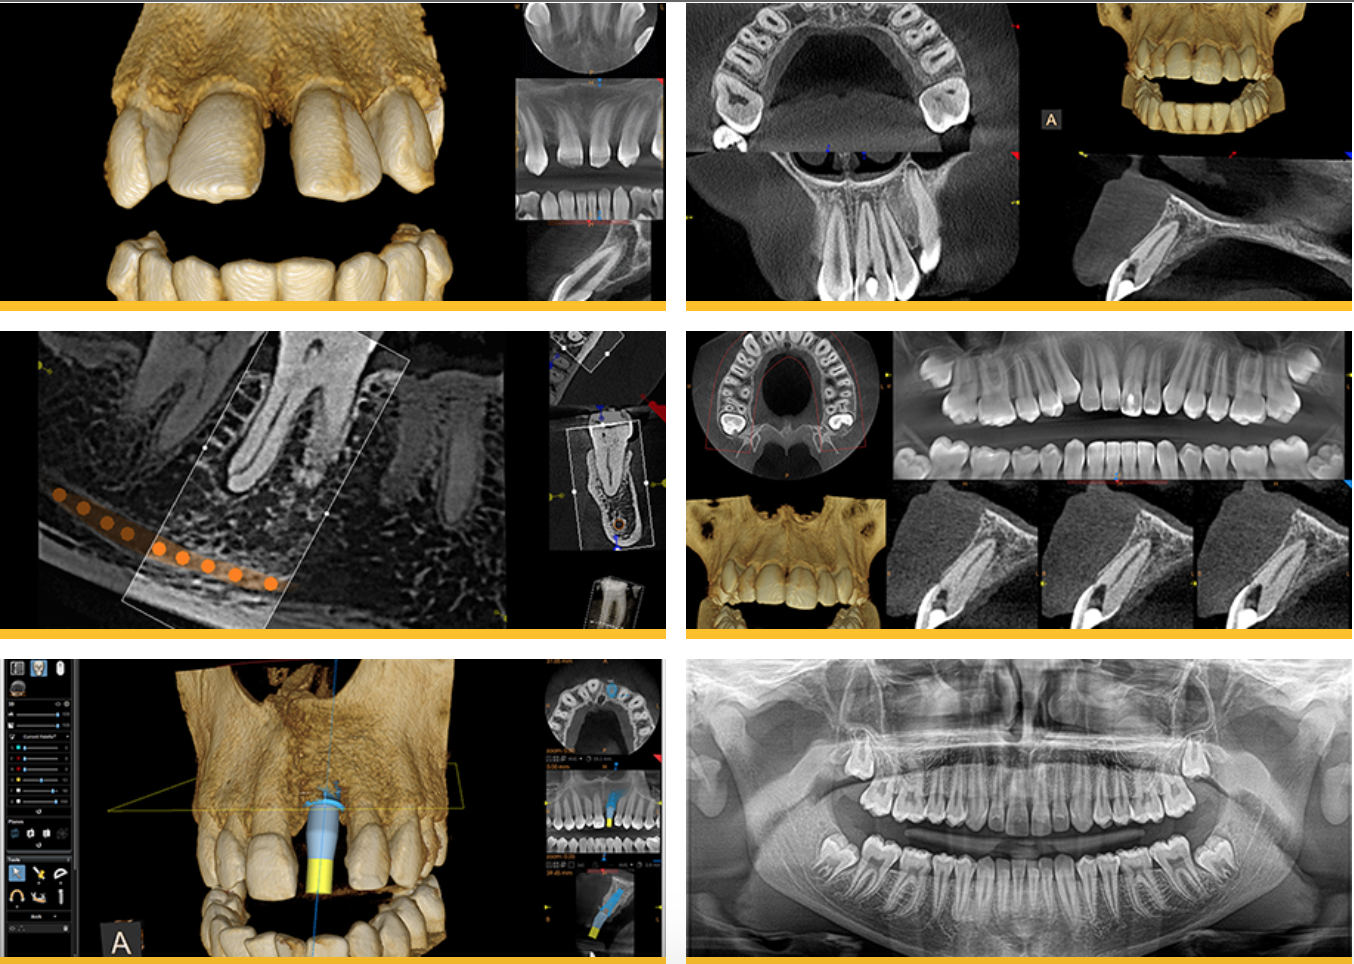

Cone Beam CT Scanning & Computer-Guided Implant Planning

Dental CT 3D imaging is becoming the standard of care in dental implantology. This 3D radiographic image provides a detailed mapping of the anatomy so that implants can be placed more quickly, more accurately, and with a much higher level of comfort and safety. Quality, predictability, and reliability of treatment is our priority at IMPrESS Perio Implant Center. In implant dentistry, we are able to provide all that with the use of the CT scan and planning software in our office.